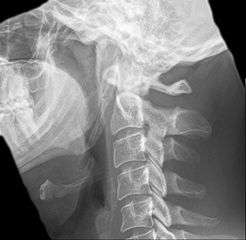

Radiograph, lateral view showing elongated stylohyoid process and stylohyoid ligament ossification